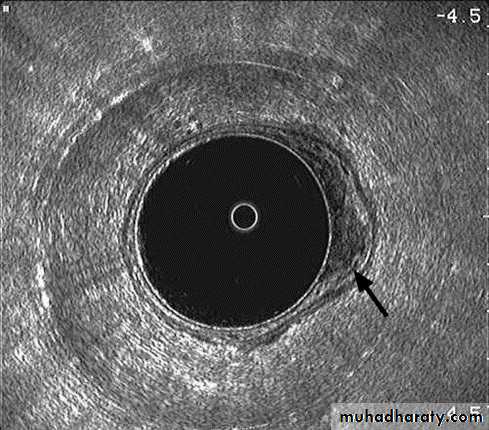

• MRI and trans-rectal US (TRUS) are able to differentiate the layers of the rectal wall. These modalities are therefore able to assess accurately the depth of invasion of rectal tumor.